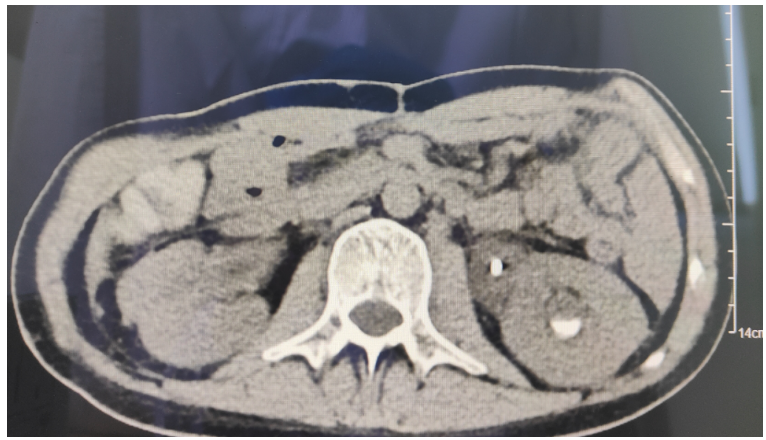

2022年7月30日开始行标准IA方案:伊达比星15 mg 第1天,20 mg第2~3天;阿糖胞苷170 mg第1~7天。病情折点:8月7日,患者体温升高38℃,血液内科予哌拉西林他唑巴坦4 g 静脉滴注q8h抗感染治疗。后患者持续发热且伴有右下腹痛,无反跳痛,肛门有排气排便。复查血常规:白细胞0.3×109/L(↓),中性粒细胞绝对值0×109/L(↓),血红蛋白64 g/L(↓),血小板8×109/L(↓)。降钙素原0.267 ng/ml;全血培养:无厌氧菌、细菌、真菌生长。腹部彩超示:38 mm×2 mm混合回声包块,右下腹肠管壁增厚,考虑为炎性包块。8月10日哌拉西林他唑巴坦升级为亚胺培南西司他丁+替加环素抗感染治疗。8月12日,发热加重,体温最高达到39.5℃,仍诉右下腹痛,未排气排便。加用卡泊芬净抗真菌治疗。8月14日,患者体温最高38℃,右下腹痛,未排气排便;复查腹部彩超: 右下腹可见一大小106 mm×36 mm混合回声包块, 考虑为炎性包块, 较前明显增大。将替加环素改为利奈唑胺。8月16日,体温无好转,全腹胀痛伴右下腹绞痛;查体:腹部叩诊呈鼓音,右下腹压痛、反跳痛,肠鸣音消失。新增诊断:腹腔感染,考虑:麻痹性肠梗阻?梗阻性肠梗阻?脓毒血症?复查腹部CT:①升结肠、回盲部及回肠末端、阑尾肠壁增厚,并低位小肠梗阻,性质待定,考虑炎症所致可能,局部肠缺血?②腹膜炎,腹水较前减少,右侧腹部皮下水肿(图1)。8月17日,血氧饱和度下降,神志呈嗜睡状态,转内科ICU,行胃镜下肠梗阻导管置管。继续抗感染治疗方案:卡泊芬净+亚胺培南+利奈唑胺。患者体温38~39℃。复查血常规:白细胞0.2×109/L(↓),中性粒细胞绝对值0.01×109/L(↓);全血培养:无厌氧菌、真菌、细菌生长;GM试验0.301 μg/L;G试验<10 pg/ml;降钙素原1.3 ng/ml(↑)。8月20日,患者体温36℃,腹胀腹痛无明显好转,右下腹局部皮肤呈黑褐色且有破溃表现(图2)。复查腹部CT:右下腹皮肤破溃膨出,较前进展(图3)。